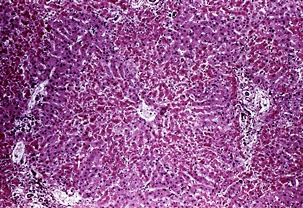

몸에 필요한 황색의 담즙색소 (빌리루빈)이 과도하게 쌓여 눈동자나 피부 등에 착색되는 현상을 말한다고 합니다. 이 담즙색소는 체내에 들어온 물질들이 분해되는 과정에서 생성되는 필요 없는 물질인데요. 일반적으로는 간에서 해독작용을 거친 후에 담즙으로 배설이 되는 것이 정상적이지만, 그렇지 못한 경우 황달이 발생하게 된다고 합니다.

황달이 생기는 이유는 담즙색소라고 알려진 빌리루빈이 과도하게 생기기 때문입니다. 빌리루빈은 우리 몸의 오래된 적혈구가 파괴되면서 생기는 물질인데요. 이 물질은 담즙에 녹아서 우리 몸의 배설물과 함께 배출이 되는 것이 정상적이지만 빌리루빈의 과잉생산이나, 간의 장애, 간세포나 담도의 손상에 의해 빌리루빈이 역류할 경우 발생된다고 합니다.